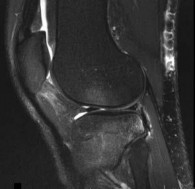

Question 12

A 30-year-old woman presents with worsening knee pain. Radiographs reveal an eccentric, lytic, expansile lesion located in the epiphysis of the proximal tibia, extending to the subchondral bone. There is no sclerotic margin. Histology demonstrates mononuclear cells and numerous uniformly distributed osteoclast-like multinucleated giant cells. Which of the following is the most effective targeted medical therapy for advanced, unresectable cases of this tumor?

Explanation

The clinical and radiographic presentation is classic for a Giant Cell Tumor of Bone (GCTB). The neoplastic mononuclear cells in GCTB express high levels of RANKL, which recruits and activates the osteoclast-like giant cells, leading to massive bone destruction. Denosumab, a monoclonal antibody against RANKL, is highly effective in treating GCTB and is used for unresectable or recurrent lesions, or as a neoadjuvant therapy.